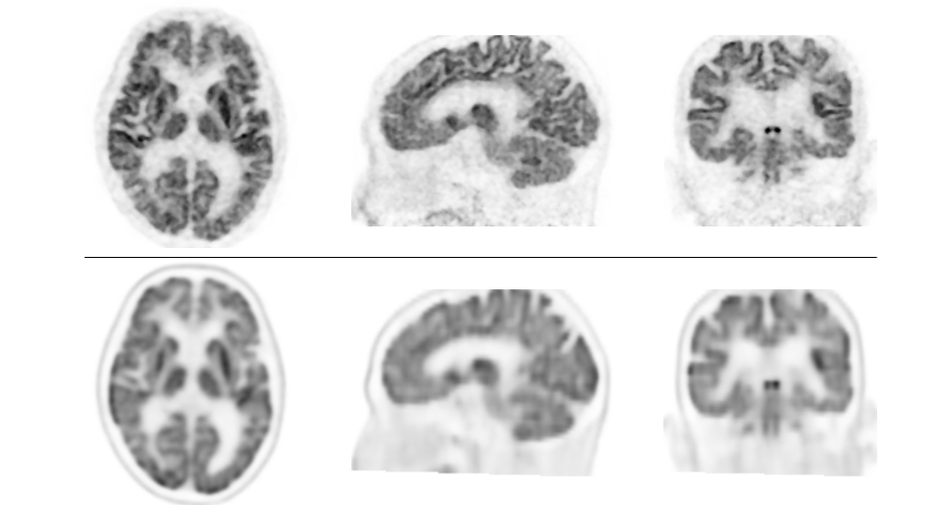

検証では、認知機能障害、てんかん等の18名の患者において、脳FDG-PET装置を用いて撮像した画像と、本PET装置で撮像した画像を比較しました。次に、認知機能障害患者17名において、従来のPET/CT装置を用いた画像と本PET装置で撮像した画像を比較しました。その結果、全例において本PET装置による画像の分解能が優れており、従来型よりも分解能が高く、細かいところまで描出できることが示されました。